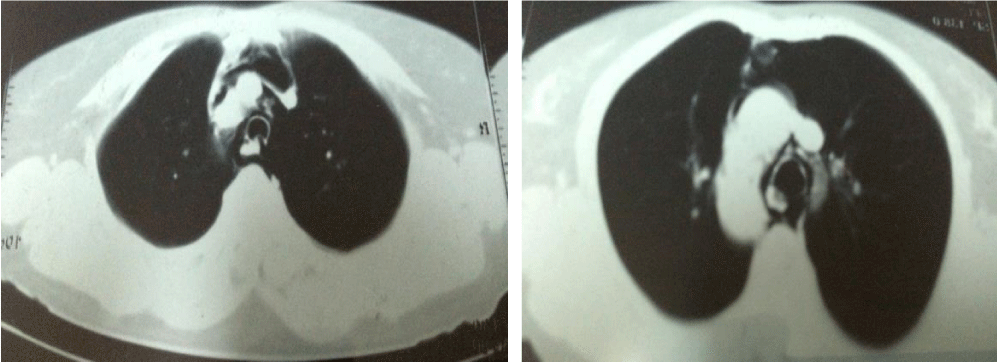

On day two, a swelling was noticed in the lower neck with crepitus on palpation suggestive of subcutaneous emphysema (Figure 2). She also complained of breathing difficulty. An urgent chest x ray was done (Figure 3) which revealed subcutaneous emphysema over lower neck, pneumomediastenum with clear lung fields without pneumothorax. Contrast Enhanced CT Scan (CECT) of thorax showed air density around trachea suggestive of pneumomediastinum (Figure 4). Lung parenchyma showed interstitial fibrosis with honey combing in basal segments of lower zones bilaterally. Her Creatine Kinase-MB values of blood samples taken 6 hours apart were within normal limits and echocardiography did not show Regional Wall Motion (RWMA) abnormality.